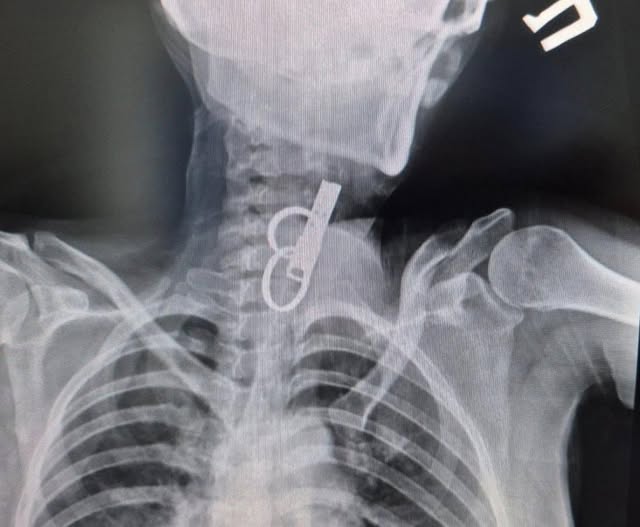

За даними "Вікон", 40-річна пацієнтка близько тижня жила з ключем у стравоході — вона проковтнула його, щоб родичі не змогли потрапити до її помешкання.

Жінку доправили до лікарні у важкому стані, тож рішення про операцію ухвалювали терміново.

Після втручання їй встановили гастростому для відновлення стравоходу. Наразі стан пацієнтки стабільний.